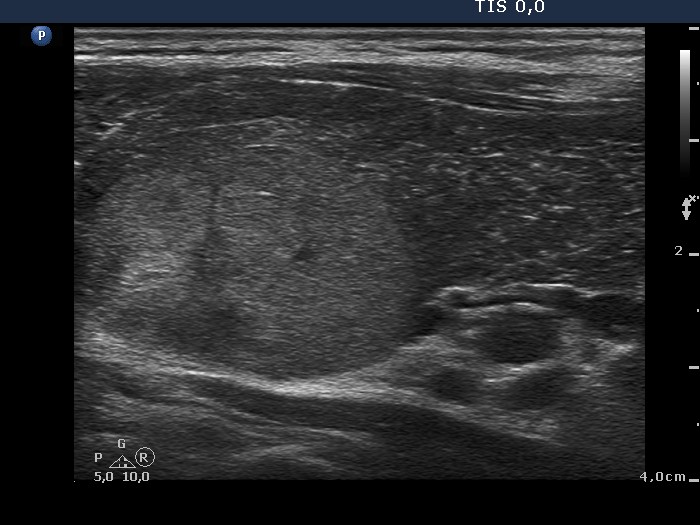

Ultrasonography. A diffusely hypoechogenic thyroid was found with extensive fibrosis. There was an echonormal nodule in the upper dorsal part of the left lobe. The nodule showed taller-than-wide shape and halo sign while the presence of perinodular blood flow was equivocal.

1. The extensive fibrotic change is a not rare situation in the case of Graves' disease. We can demonstrate the possible misinterpretation of granular presentation of fibrosis - see comment to ultrasonographic picture.

2. Malignancy occurs only exceptionally in an echonormal nodule except for autoimmune thyroid disorders. We must be aware that the echo structure of a nodule may be influenced by the echo structure of the non-nodular thyroid. Therefore, echonormal nodules are targets of cytological investigation in hypoechogenic thyroids, i.e. Graves' disease and in Hashimoto's thyroiditis.

3. The presence of perinodular blood flow is doubtful because the nodule is avascular while the vascularization of the extranodular part is extremely increased. Nevertheless, the nodule proved to be encapsulated on histopathology.

6. The histogram value of the nodule proved to be 74.8, a value which is less than the average of the normal parenchyma, therefore in absolute sense, this is a minimally hypoechoic nodule. In relative sense, compared to the non-nodular part of the particular case, the nodule is hyperechoic.